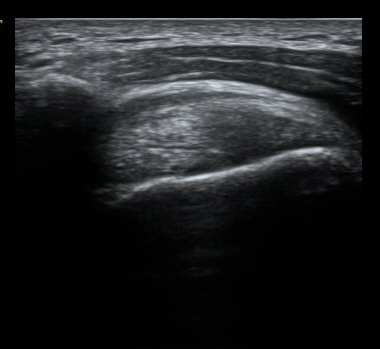

À̵ιڱٰí¶û¿¡¼­ À̵ιڱÙÀÌ Á¤»óÀûÀ¸·Î °üÂûµÇ°í ƯÀÌ ¼Ò°ßÀ» º¸ÀÌÁö ¾ÊÀ½(±×¸² 2).